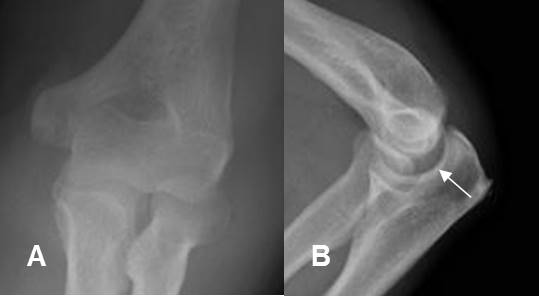

Fig 159. Subluxación.

A: Rx AP. No se identifican alteraciones.

B: Rx lateral. Aumento del espacio entre el epicóndilo medial y la cavidad coronoides, por subluxación.